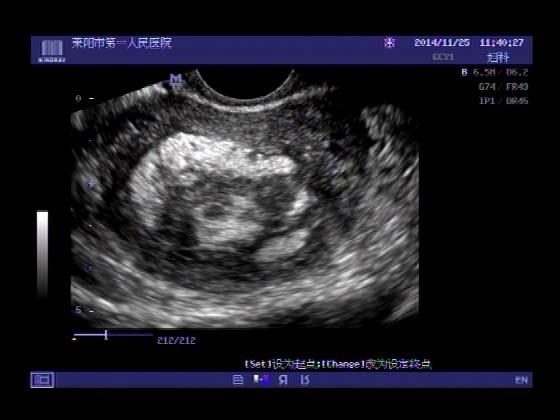

超声入门贴379---------粘膜下肌瘤(阴超的魅力)

女,43岁,月经量多3个多月,加重一个月

外院彩超检查提示:子宫后肌壁略高回声团------肌瘤?息肉?,盆腔少量积液

今天来我院检查:

巧妇难为无米之炊,经腹部超声确实很难定,阴超一目了然,乡镇医院诊断水平的提高更迫切的需要高档仪器的引进!